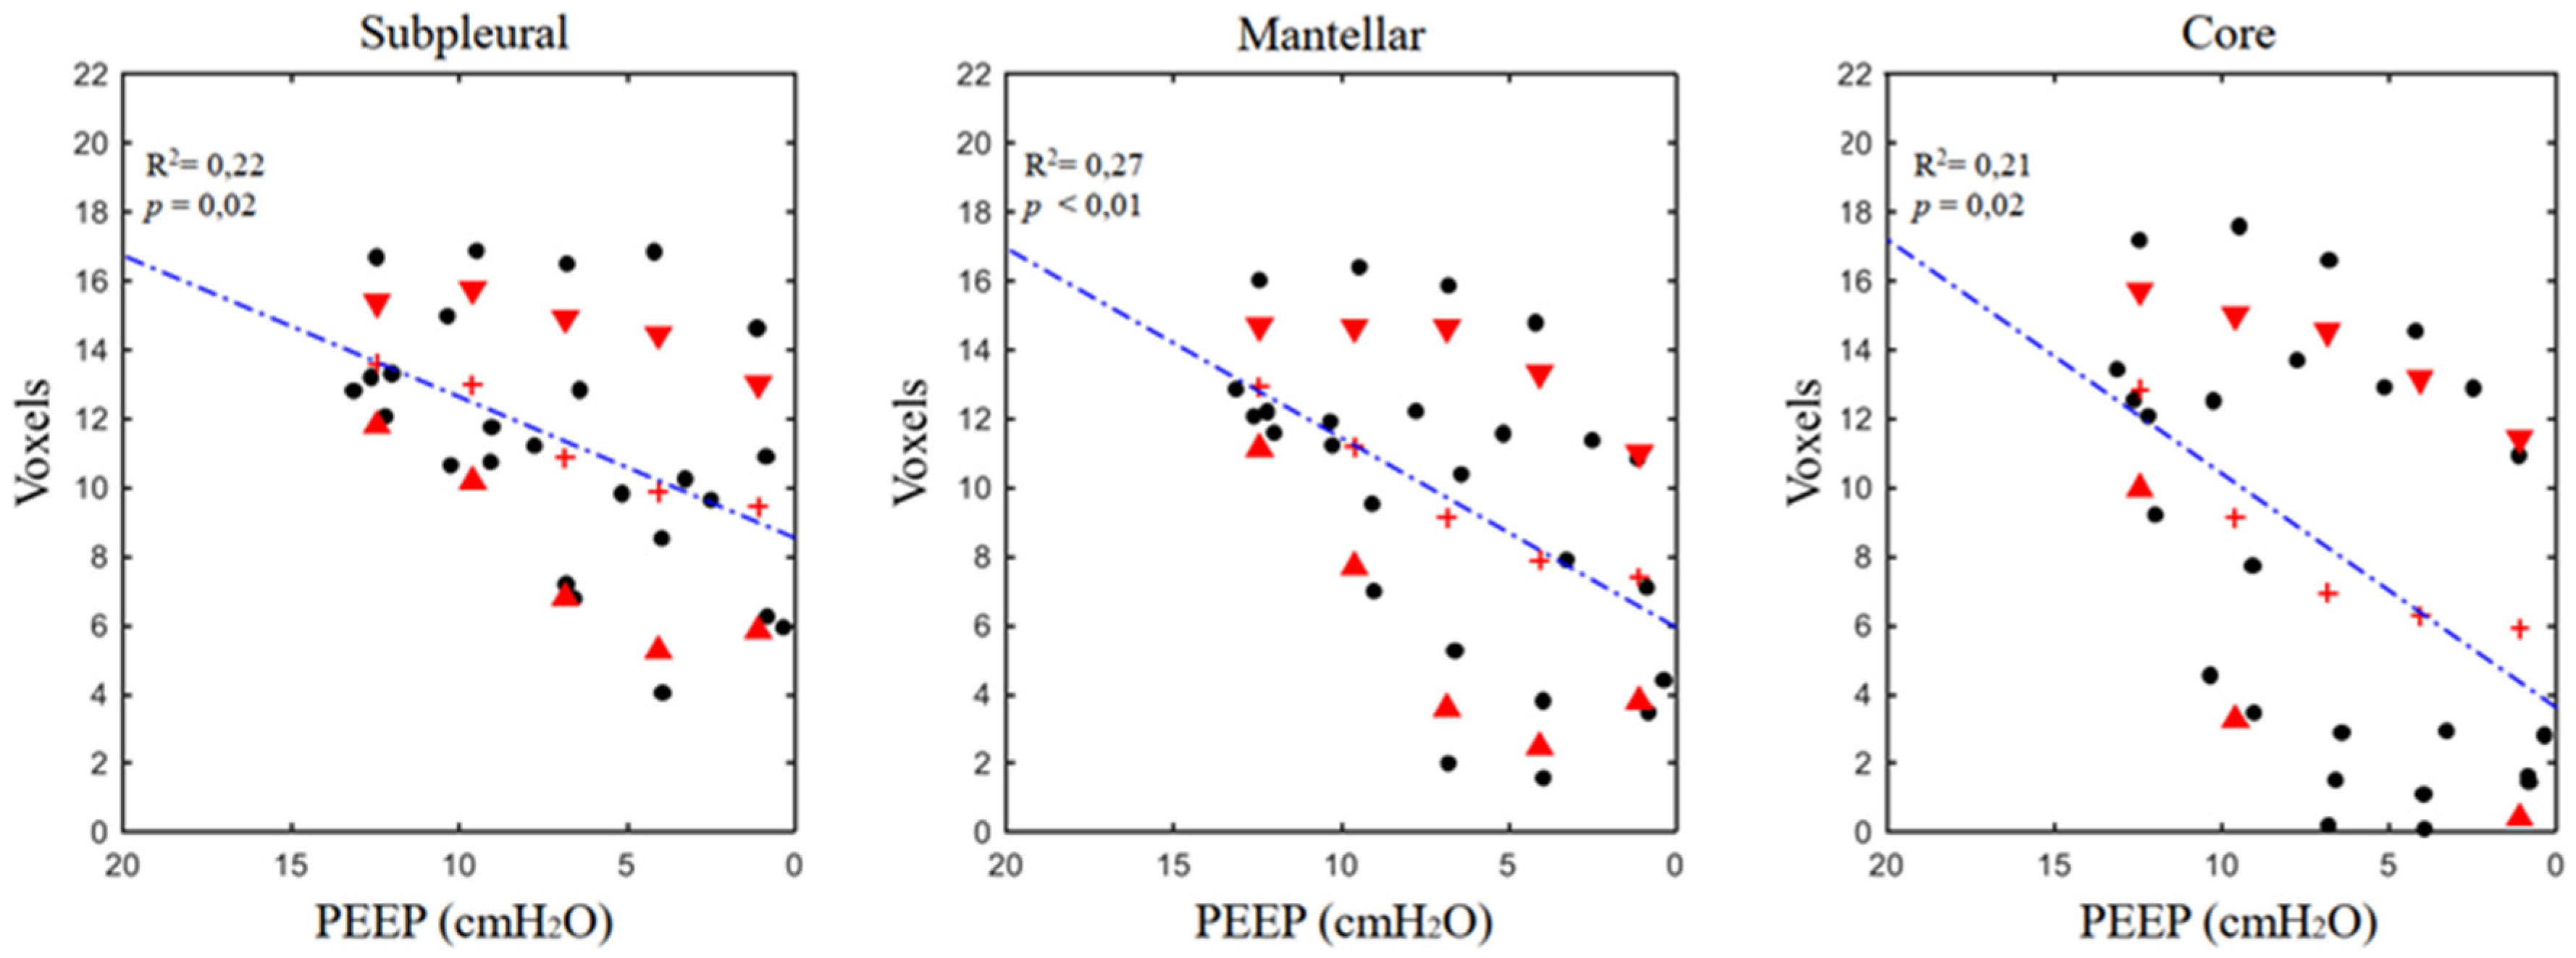

3.2. Airspaces Number and Dimension in the Three ROIs

| ROI | PEEP 12 | PEEP 9 | PEEP 6 | PEEP 3 | PEEP 0 | m | k | R2 | p | ||

| Regional analysis | ASdim (voxel) | SUB | 13.6 ± 1.8 | 13 ± 2.8 | 10.9 ± 4.1 | 9.9 ± 4.6 | 9.4 ± 3.6 | 0.41 | 8.54 | 0.22 | 0.02 (*) |

| MAN | 12.9 ± 1.8 | 11.2 ± 3.5 | 9.1 ± 5.5 | 7.9 ± 5.4 | 7.4 ± 3.6 | 0.55 | 5.95 | 0.27 | <0.01 (*) | ||

| COR | 12.9 ± 2.9 | 9.1 ± 5.9 | 6.9 ± 7.6 | 6.3 ± 6.9 | 5.9 ± 5.5 | 0.68 | 3.61 | 0.21 | 0.02 (*) | ||